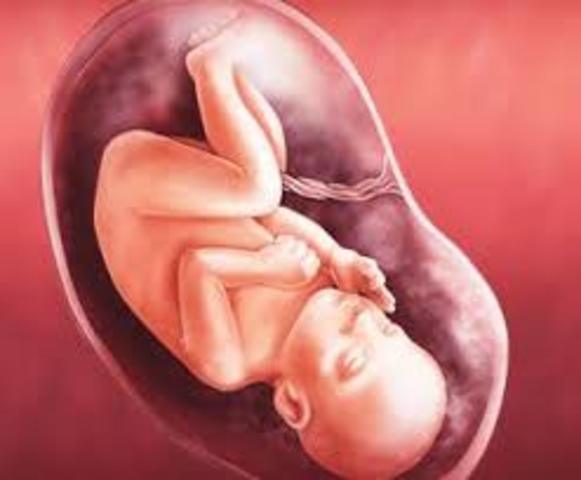

Ya son 20 semanas de embarazo, ¡has llegado a la mitad del embarazo! Solemos hablar de 40 semanas de embarazo a partir de la última menstruación. Sin embargo, la duración puede variar de 37 a 42 semanas. En la semana 20 de embarazo el bebé mide aproximadamente 16 cm largo y pesa cerca de 255 gramos pero, como sabrás, al bebé le falta mucho por crecer.

A las 21 semanas de embarazo el bebé ya es muy activo y no para de moverse. Según indican estudios médicos, el bebé en esta etapa se suele mover alrededor de 50 veces cada hora.. ¿lo notas? Todos esos movimientos sirven para estimular su correcto desarrollo físico y mental. Además, con 21 semanas ya respira y traga líquido amniótico preparándose para respirar y digerir cuando nazca. Si vas a tener una niña, sus ovarios tendrán más de 6 millones de óvulos

Al llegar a la semana 22 de embarazo, la piel delgada y rojiza del bebé está cubierta por una sustancia gruesa, blanca y cerosa llamada vernix o unto sebáceo. Ésta protege la piel del bebé contra las sustancias del líquido amniótico. De ahora en adelante se empiezan a desarrollar sus sentidos, especialmente los del tacto y del gusto.

En la semana 23 del embarazo, se está depositando el pigmento que colorea la piel del bebé. Ésta tiene una apariencia arrugada que se alisará en las próximas semanas. Al mismo tiempo, empezará a desarrollar su cerebro con rapidez. Sus medidas empiezan a ser más proporcionadas.

Alrededor de la semana 24 de embarazo, el feto empieza a percibir los primeros estímulos del mundo exterior. Casi todos sus pequeños órganos sensoriales (oído, olfato, papilas gustativas y nervios del tacto) están ya maduros. Esta etapa es clave porque tu bebé empieza a interpretar el mundo, a interactuar, explorar, aprender. Para empezar, se va familiarizando con olores y sabores del exterior y de la propia madre (como los de la leche) a través del líquido amniótico.

sabemos que a las 25 semanas de embarazo el niño ya tendrá pestañas. Sin embargo, el color de los ojos no se desarrolla por completo. Esto se debe a que algunos pigmentos necesitan luz para acabar de formarse. De hecho, los ojos de tu bebé pueden cambiar en las primeras semanas de vida. Los asiáticos y los africanos nacen con ojitos marrones o grises y acaban teniéndolos oscuros o negros.

A partir de la semana 26 de embarazo el pequeñín hará sus primeros gestos y arrumacos. Igualmente, empezará a hacer uso de más reflejos importantes como el reflejo labial de succión, dado que empieza a chuparse el dedo con virulencia. La mayor parte del día, tu bebé estará durmiendo.